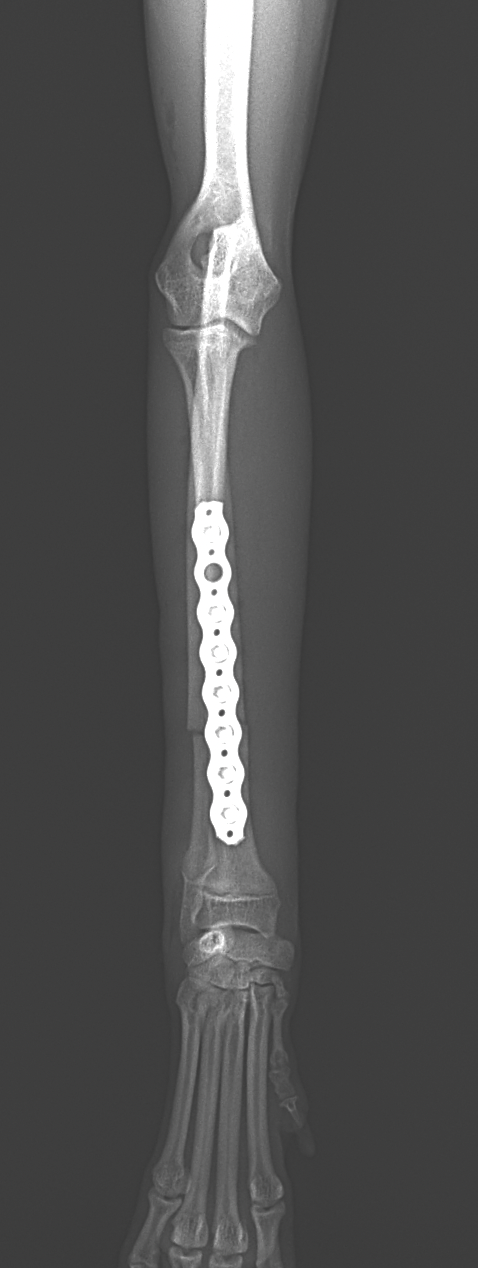

ドッグランで遊んでいた所、他のワンちゃんと接触して橈骨骨折をしたとのことでかかりつけ医より、若い子犬が紹介受診されました。橈骨骨幹部を1.5 Titanium Locking Plateで固定術を行いました。子犬には辛いですがしばらく安静が必要です。